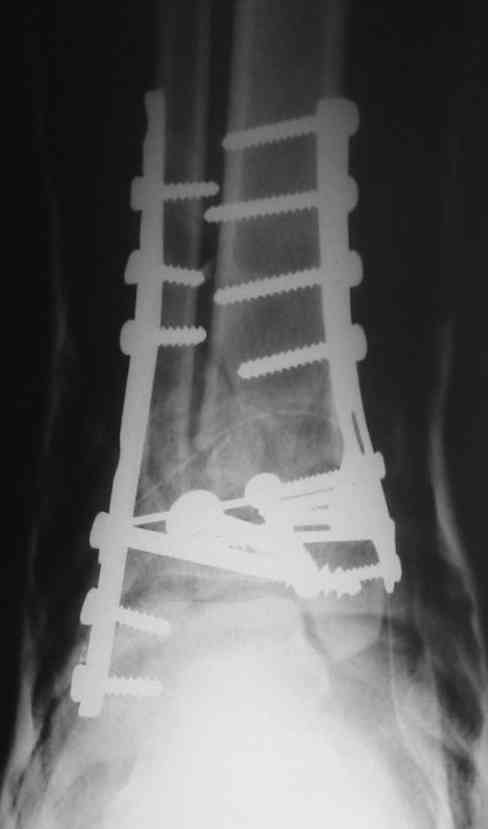

OK, Dr Driagin, Ja operiroval bolnogo po Vashemu, hotia sam ni ochen' ubezden' v itom, t.k. bolnoi otkazalsa na proch' ot ex.fix, ja emu sdelal ORIF + Kostnia plastika, snimky prelogiottsa,

Очень прилично получилось, но мне показалось, что винты на 4,5 мм.Это принципиально винты используются 3,5 и 4,0 мм. И проекцию прямую бы переделать. С уважением Дрягин

На представленном снимке видно, что эпифиз смещен латерально.

Сейчас с этим ничего не сделать, похоже.

Однозначно сказать сложно.Расстояние между тараном и медиальной лодыжкой меньше чем между тараном и крышей большеберцовой кости.Это может быть за счёт не правильной укладки.Пока не отчаиваетесь.Главное вы поняли принцип.Сделайте несколько проекций прямых и посмотрим.Для всех интересно.С уважением

Мне кажется, что все конечно далеко от идеала. Сложный перелом. Есть ощущение, что малоберцовая кость (ключ!) фиксирована с ротацией и удлинением. Снимки конечно необходимо сделать в правильных проекциях и без гипса...

В голеностопном суставе обязательны 3 стандартные ренгенологические проекции: прямая, латеральная и мортиз. Без них невозможно трактовать состояние голеностопа.